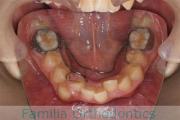

- ≫治療前

上顎

下顎

前歯の関係など

右側

正面

左側